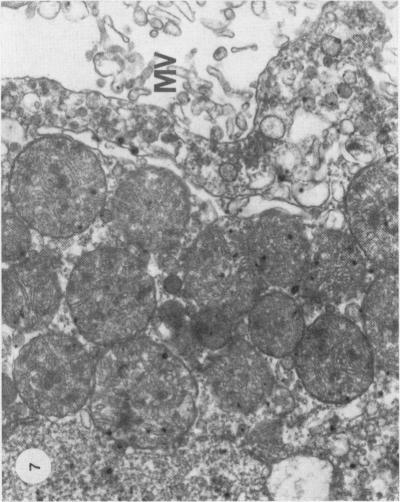

In JCLR and Wistar-Porton rats renal concentrations of Cd2+ were maximal (21-22 micrograms Cd2+/g wet wt tissue) at 1 and 4 h respectively after the administration of CdCl2 (10 micromol, 1-12 mg Cd2+/kg body wt) together with L-cysteine (5 mmol/kg body wt). Synthesis of metallothionein in the kidney in response to the uptake of Cd2+, which occurred between 2 and 7 h after treatment in the Wistar-Porton rat, affected the distribution of Cd2+ between proteins of the renal soluble fraction, but not between the particulate components and, at both times, about 40% of the total Cd2+ was associated with the heterogeneous nuclei + cell debris fraction. Autoradiographic studies with 109CdCl2 revealed that Cd2+, accumulated by the kidney under these conditions, was not uniformly distributed throughout the renal cortex, but was concentrated unevenly in proximal tubules in the outer stripe of the outer zone of the medulla. Pathological changes, which were correlated with the concentrations of accumulated Cd2+ and were limited to the S3 segments of the proximal tubules, were apparent by light microscopy at 4 h after the administration of Cd2+ + cysteine and progressed with time. Thus by 7 h the lesion had extended to include almost the whole of the outer stripe of the outer zone of the medulla and, by 24 h the cells of the affected epithelia showed extensive necrosis and karyorrhexis. At this, as at earlier times, the cortex appeared to be undamaged. Neither these nor other morphological changes were observed in the kidneys of animals that had been dosed with either Cd2+, or L-cysteine alone. Within 60 min of the administration of Cd2+ + cysteine an increase in the number of endocytotic vesicles in the apical cytoplasm of the proximal tubular epithelium was observed by electron microscopy. Subsequent cytoplasmic vesiculation, which was conspicuous at 2 h, was extensive and widespread in both the apical and basal regions of the cytoplasm at 4 h. In some cells at this time the nuclei were irregular in shape; the mitochondria were swollen and their cristae were disorganized. As, after the administration of either Cd2+ or cadmium-metallothionein, damage is known to occur in the S1 and S2 segments of proximal tubules throughout the cortex, the Cd2+ + cysteine combination does not provide an exact model which reproduces in a short time the effects of long-term, low level exposure to Cd2+. Nevertheless it is suggested that the toxic mechanisms are the same after either treatment with Cd2+ + cysteine or continual exposure to Cd2+, but are limited to different segments of the proximal tubules. Possible mechanisms of toxicity are discussed.

在JCLR大鼠和Wistar-Porton大鼠中,在给予氯化镉(10微摩尔,1-12毫克镉离子/千克体重)和L-半胱氨酸(5毫摩尔/千克体重)后,肾脏中镉离子的浓度分别在1小时和4小时达到最大值(21-22微克镉离子/克湿重组织)。在Wistar-Porton大鼠中,处理后2至7小时内,肾脏中因摄取镉离子而合成的金属硫蛋白影响了镉离子在肾脏可溶性部分蛋白质之间的分布,但不影响颗粒成分之间的分布,并且在这两个时间点,总镉离子的约40%与异质核+细胞碎片部分相关。用109氯化镉进行的放射自显影研究表明,在这些条件下肾脏积累的镉离子并非均匀分布于整个肾皮质,而是不均匀地集中在髓质外带外层的近端小管中。与积累的镉离子浓度相关且局限于近端小管S3段的病理变化,在给予镉离子+半胱氨酸后4小时通过光学显微镜可见,并随时间进展。因此,到7小时时,病变已扩展至几乎包括髓质外带外层的全部,到24小时时,受影响上皮细胞出现广泛坏死和核碎裂。此时,如同早期一样,皮质似乎未受损伤。单独给予镉离子或L-半胱氨酸的动物肾脏中未观察到这些或其他形态学变化。在给予镉离子+半胱氨酸后60分钟内,通过电子显微镜观察到近端小管上皮细胞顶端细胞质内吞小泡数量增加。随后的细胞质空泡化在2小时时明显,在4小时时在细胞质的顶端和基部区域广泛且普遍存在。此时在一些细胞中,细胞核形状不规则;线粒体肿胀且嵴紊乱。由于已知在给予镉离子或镉-金属硫蛋白后,整个皮质近端小管的S1和S2段会发生损伤,镉离子+半胱氨酸组合并不能提供一个能在短时间内重现长期低水平接触镉离子影响的精确模型。然而,有人认为,用镉离子+半胱氨酸处理或持续接触镉离子后的毒性机制相同,但局限于近端小管的不同段。文中讨论了可能的毒性机制。